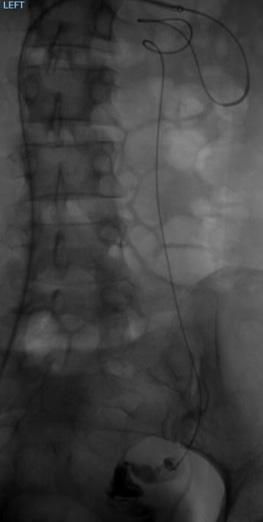

DeepQure advances clinical trials of its HyperQure extravascular renal denervation system

DeepQure recently detailed progress in clinical trials of its extravascular renal denervation device, HyperQure.

The company is actively conducting clinical trials in both South Korea and the USA, which it says demonstrate “promising” results. In South Korea, seven patients have undergone the procedure, showing meaningful reductions in blood pressure without any adverse events during- or post-operation.

The company aims to complete enrolment for its Korean clinical trial within the first quarter of 2025.